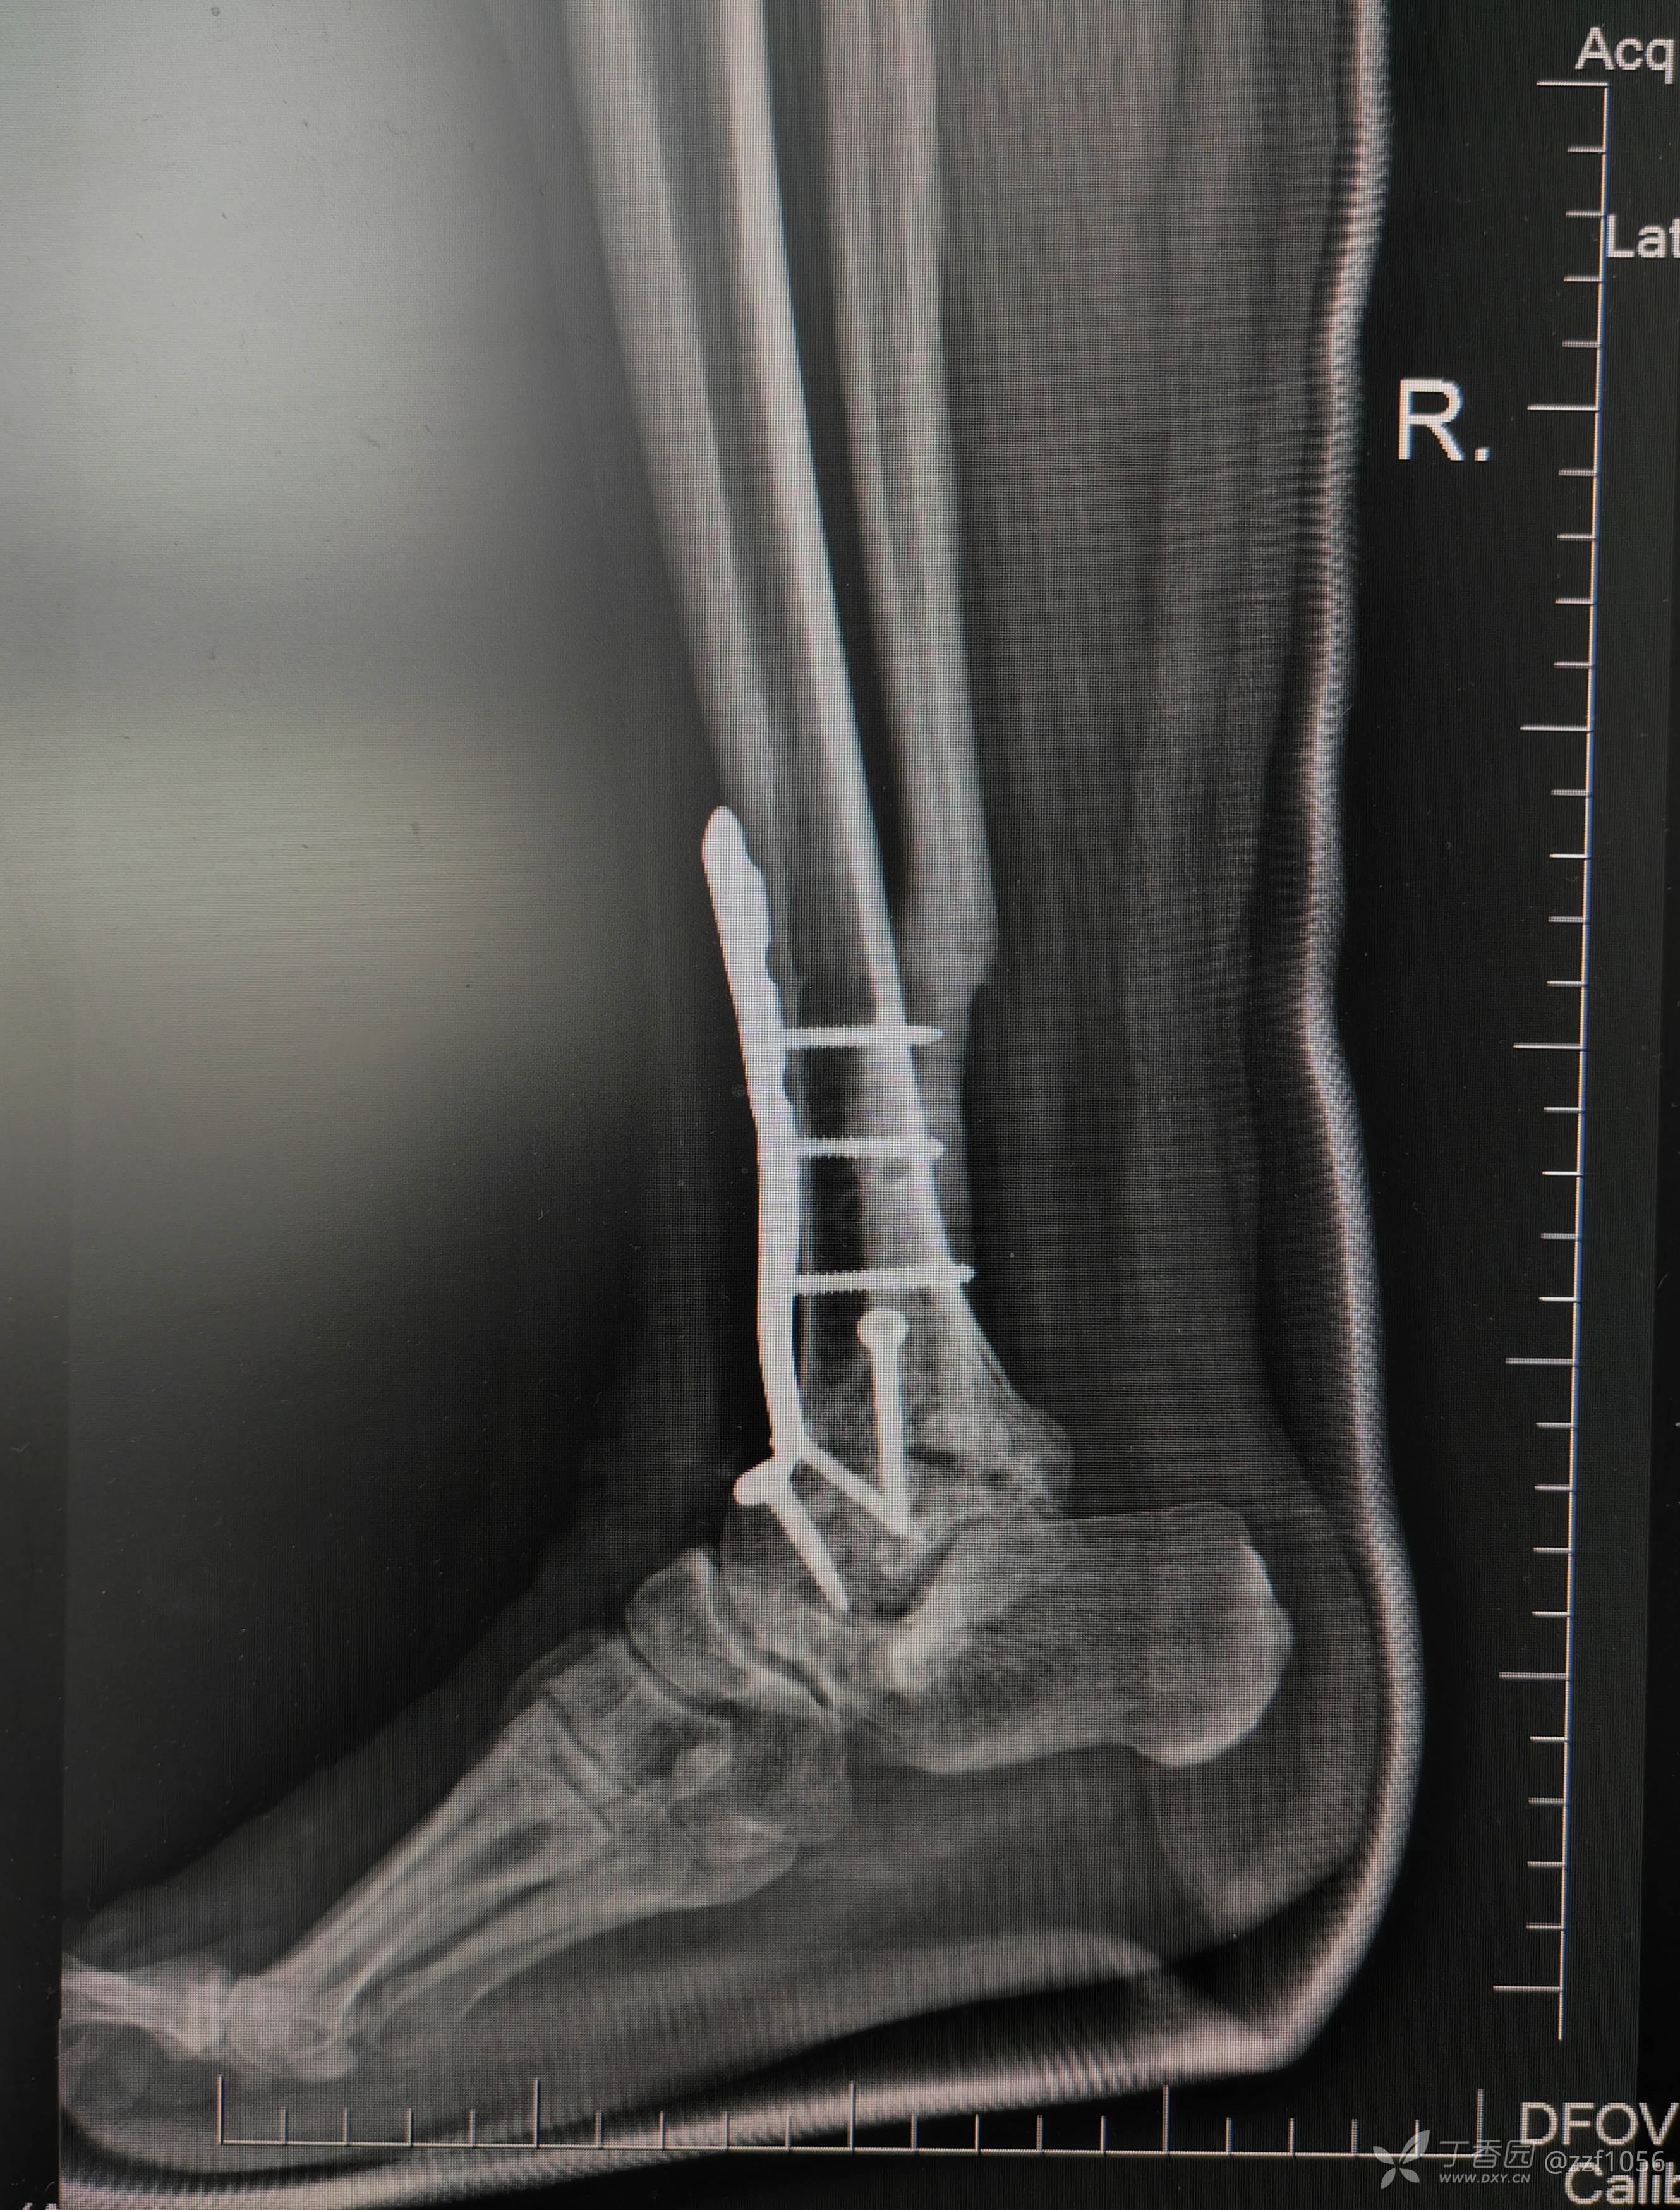

术后

就备了一块融合钢板,偏长了点

应该是90°➕

总体满意